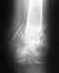

снимок 26.07.11, после которого сказали опять носить лангету так как я чувствовал легкое давление в месте перелома при движении кистью